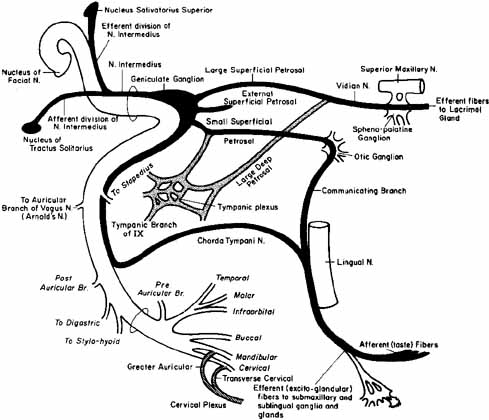

review. Am J Phys Med Rehabil 67:137, 1988 33. Morgan M, Nathwani D: Facial palsy and infection: The unfolding story. Clin Infect Dis 14:263, 1992 34. Adour KK: Medical management of idiopathic Bell's palsy. Otolaryngol Clin North Am 24:666, 1991 35. Hyden D, Roberg M, Forsberg P: Acute idiopathic peripheral facial palsy: Clinical, serological, and cerebrospinal